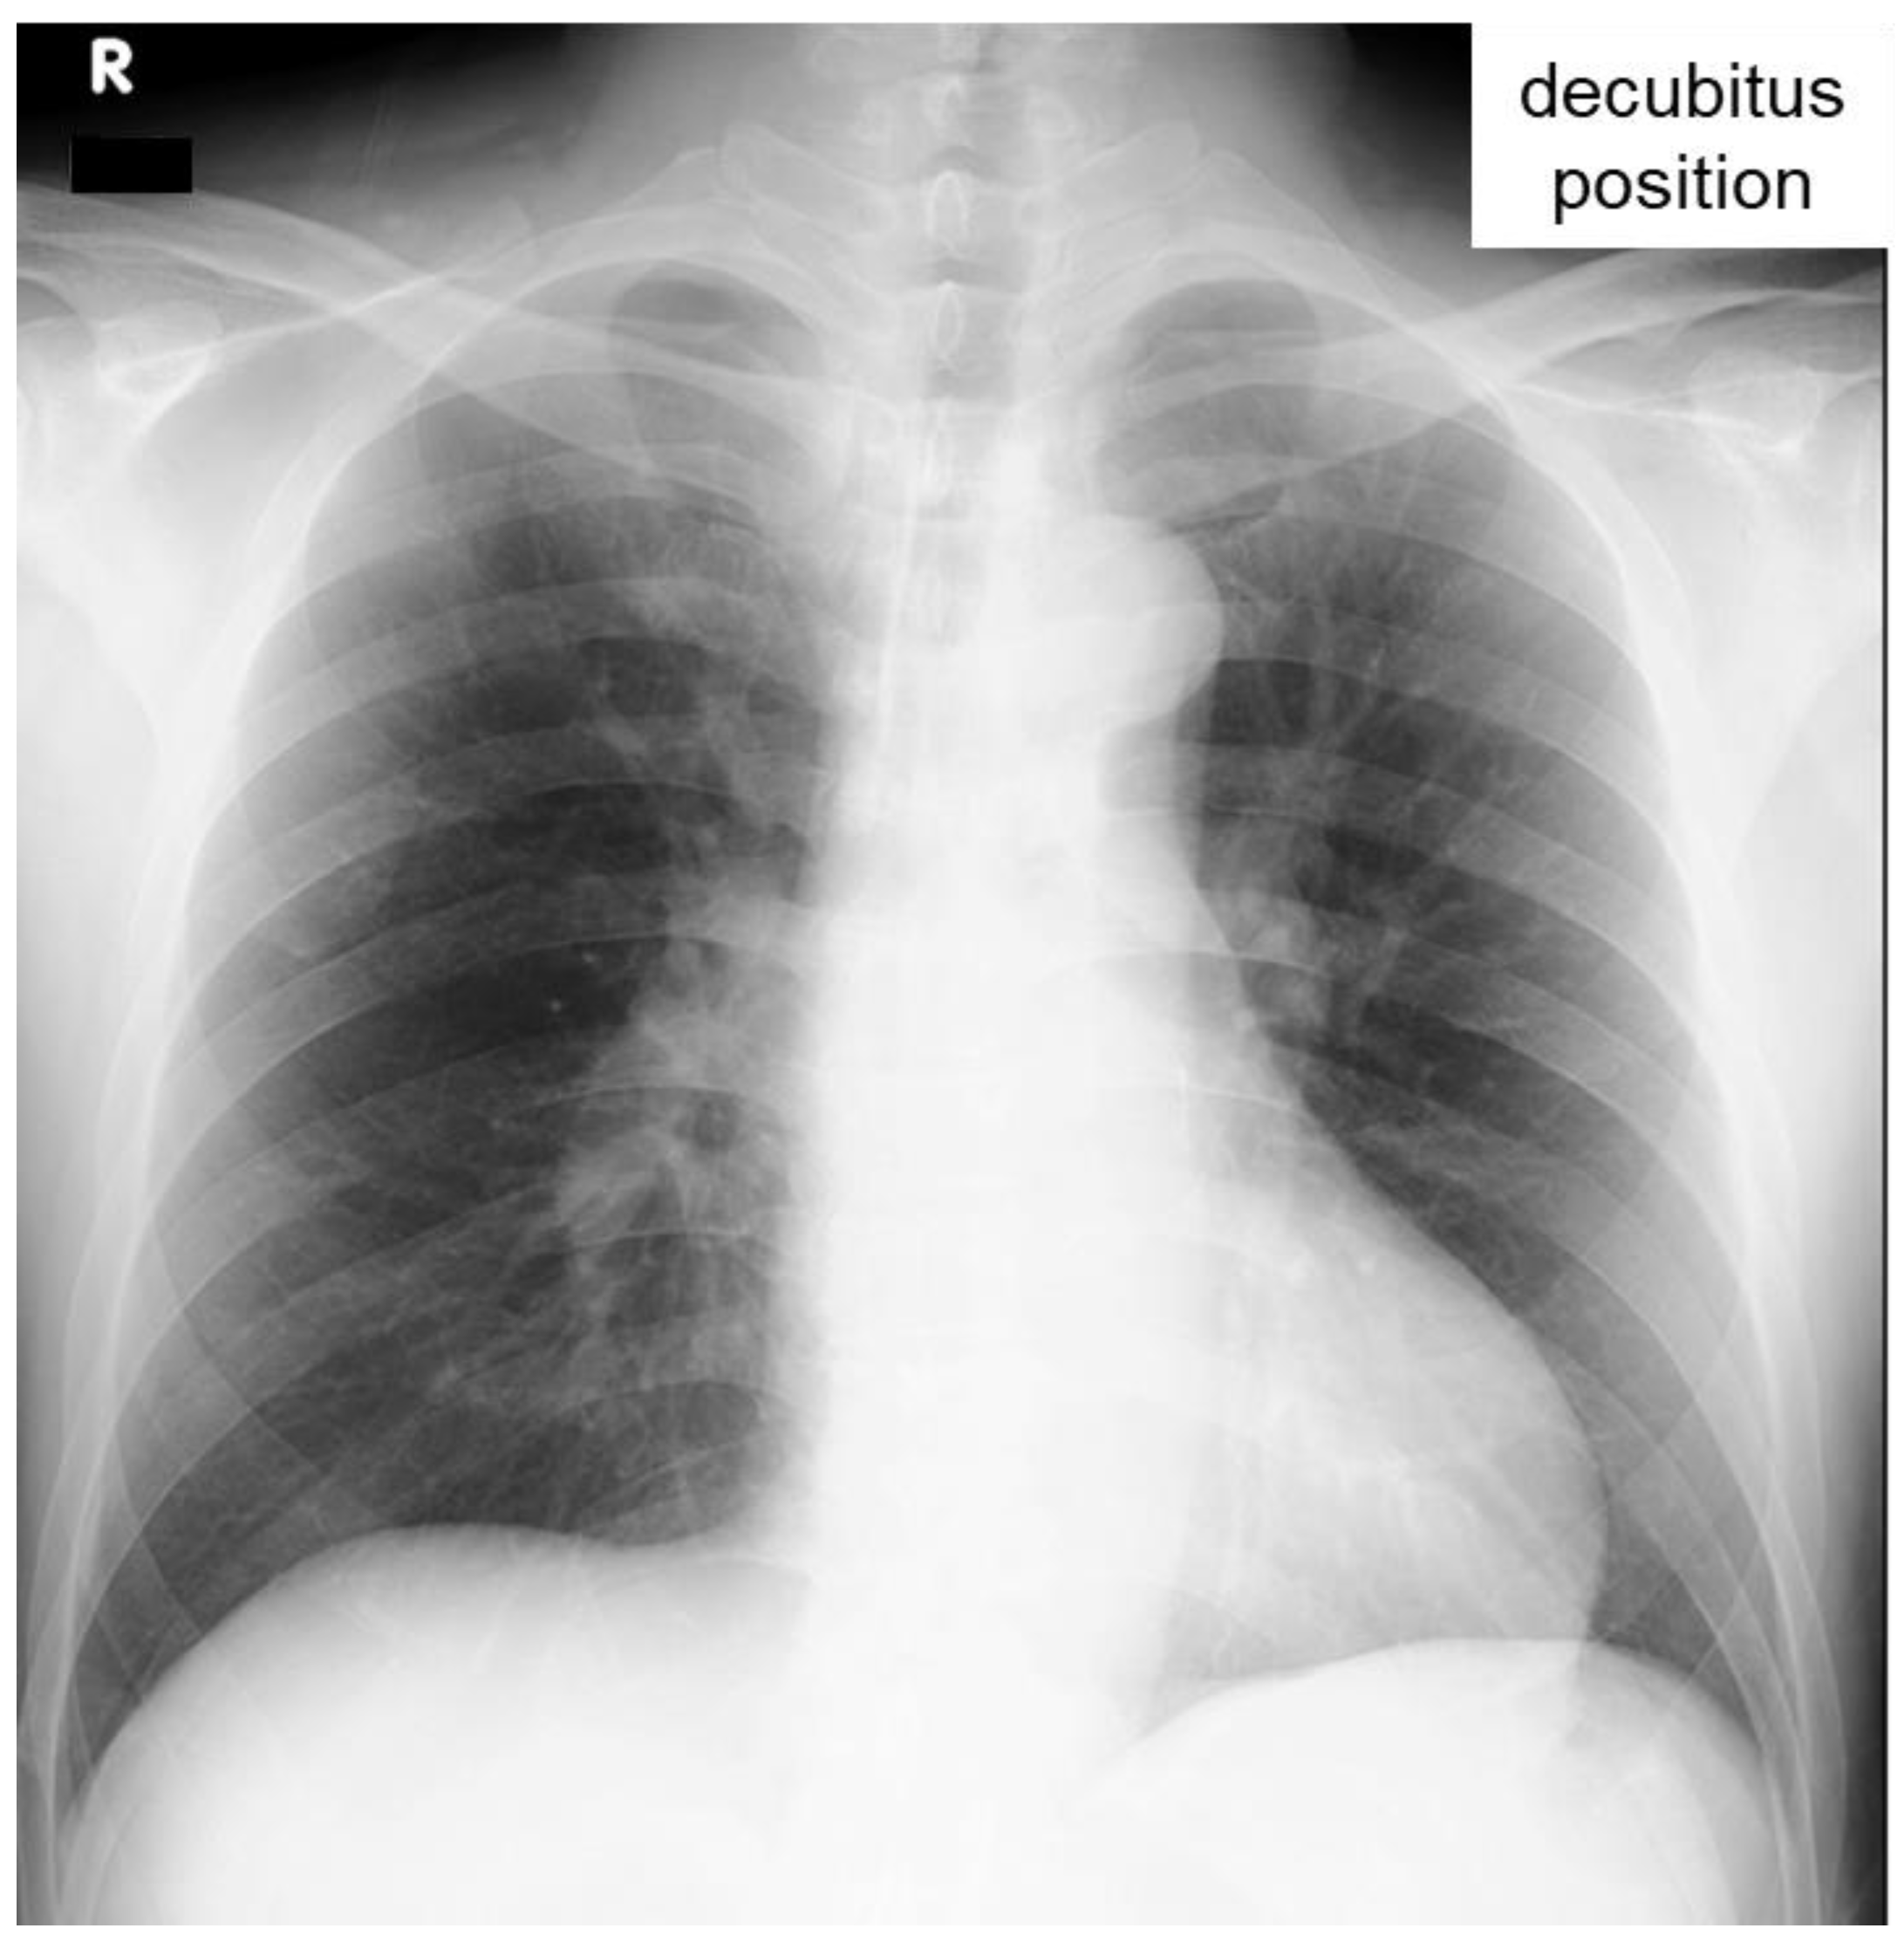

On the 12-lead ECG, heart rate of 98 beats/min, sinus rhythm, a positive axis, clear Q waves, and negative T waves during induction III were observed. Chest radiography (Figure 1) demonstrated slightly increased permeability in the bilateral middle lung fields. In transthoracic echocardiography (Figure 2), both left and right ventricles were of normal in size, as seen on the parasternal left border long-axis tomogram and parasternal left border short-axis tomogram, with no evidence of left ventricular compression. In the four-chamber view, the right ventricle seemed to be slightly enlarged. The tricuspid valve systolic pressure gradient was 22.5 mmHg. Chest contrast-enhanced CT revealed thrombi in the bilateral main pulmonary arteries (Figure 3). Abdominal contrast-enhanced CT revealed thrombi in the IVC duplication, left common iliac vein, left IVC, and left renal vein (Figure 4). The left IVC was slightly smaller in diameter than the normal IVC (right IVC). It branched from the left renal vein and descended alongside the left kidney to contact the left common iliac vein. A tributary branch to the right IVC was observed immediately before it joined the left common iliac vein. The left femoral vein similarly demonstrated a few low-absorption areas, suggestive of thrombi.

Figure 2. Transthoracic echocardiography. Transthoracic echocardiography showed that both left and right ventricles were of normal size, as seen on the parasternal left border long-axis tomogram (a) and parasternal left border short-axis tomogram (b), with no evidence of left ventricular compression. In the four-chamber view (c), the right ventricle seemed to be slightly enlarged.